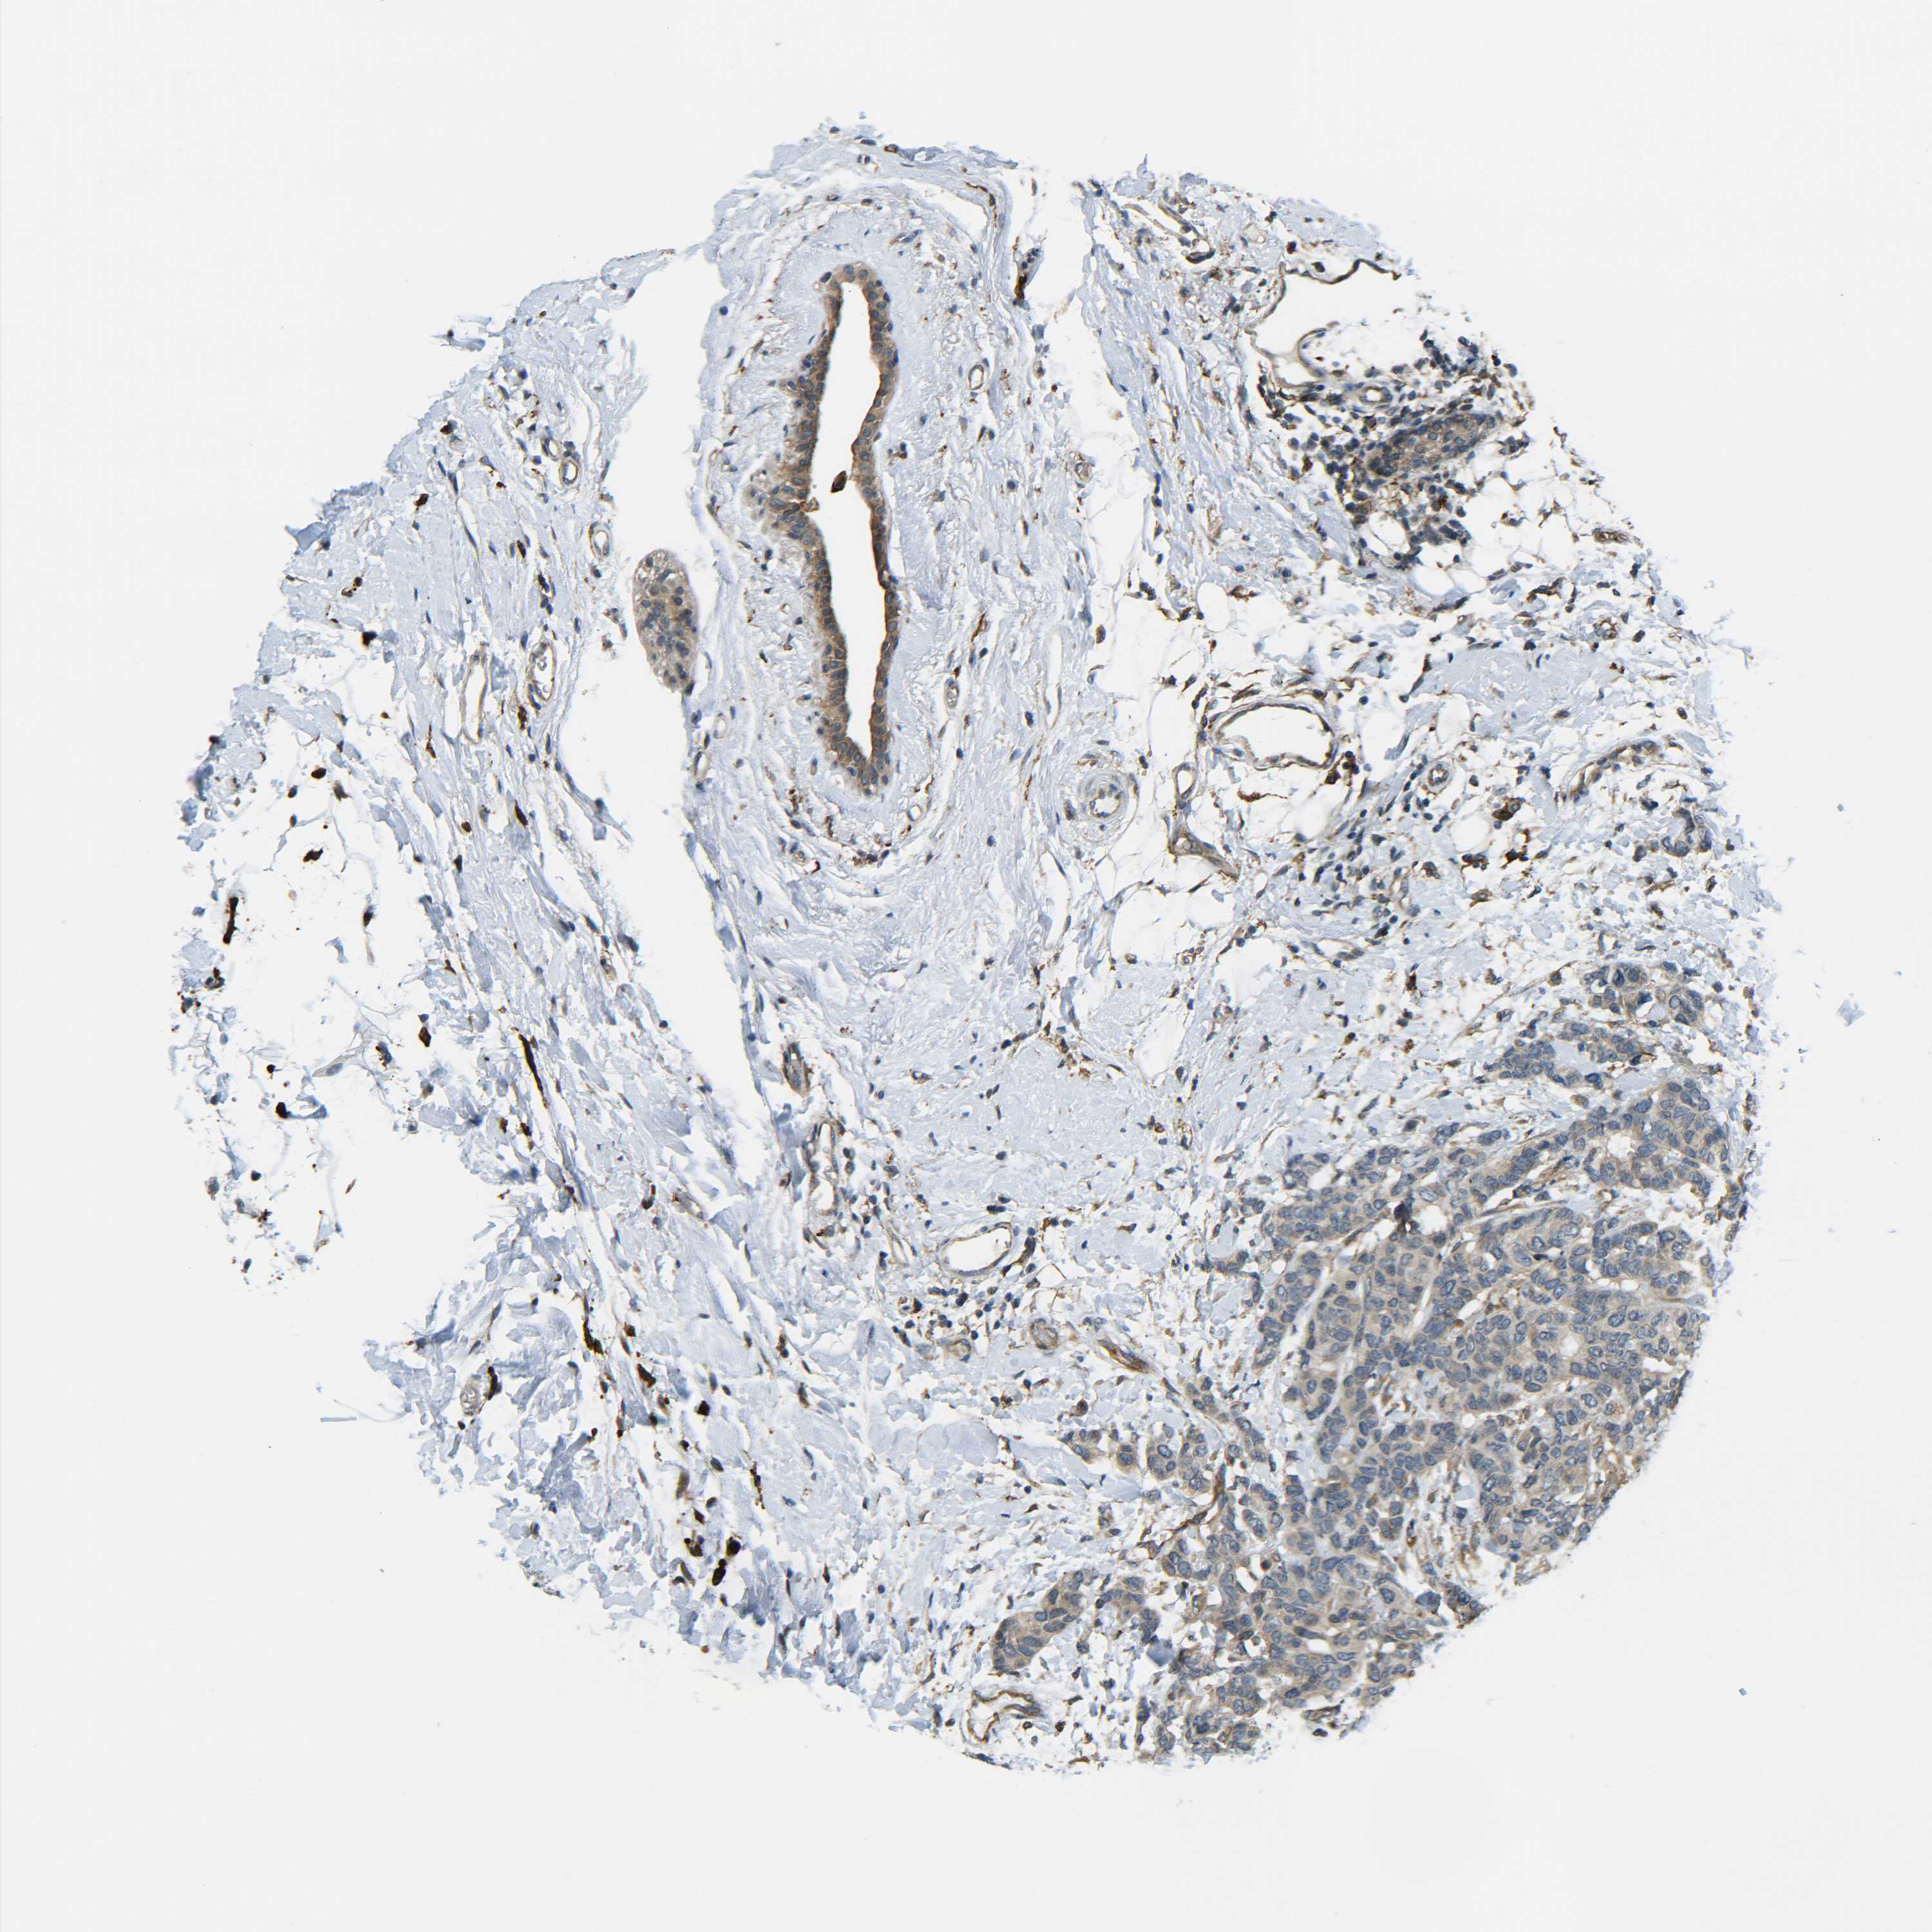

CANCER BREAST CANCER Show tissue menu

BRCA TCGA BRCA VALIDATION PROTEIN EXPRESSION